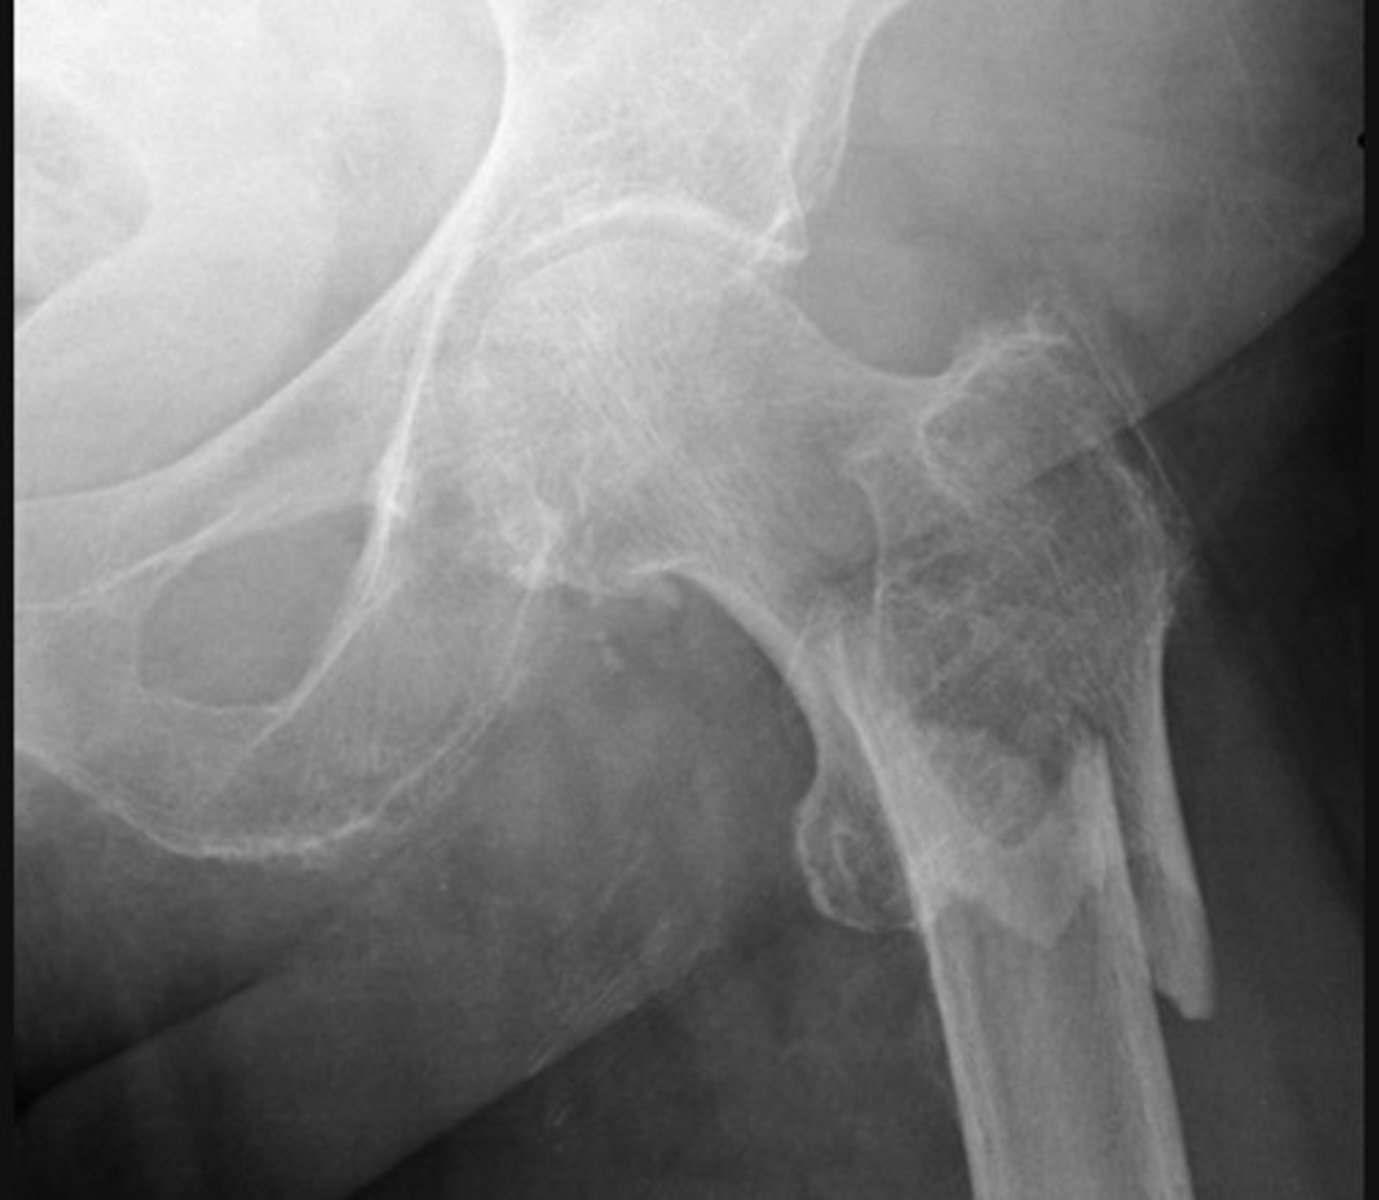

Subtrochanteric fracture

The bone texture is abnormal in this patient with a known malignancy - indicating a pathological fracture

A fracture of the femoral neck is accompanied by avulsion of the greater trochanter